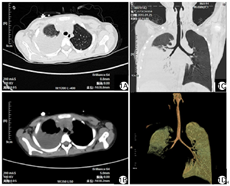

实验室和辅助检查:血常规:白细胞计数(white blood cell count,WBC) 5.06×109/L,中性粒细胞百分比(neutrophils%,N% )40.9 %,红细胞计数(red blood cell count,RBC) 4.22×1012/L,血红蛋白(hemoglobin,Hb)115 g/L,血小板计数(platelet count,PLT) 202×109/L。尿、粪常规正常。血生化大致正常。血清乳酸脱氢酶(lactate dehydrogenase,LDH)859 U/L。C反应蛋白(C reactive protein,CRP)112.7 mg/L。红细胞沉降率(erythrocyte sedimentation rata,ESR)94 mm/h。降钙素原(procalcitonin,PCT)0.51 μg/L。凝血:国际标准化比值(international normalized ratio,INR)1.21,活化部分凝血活酶时间(activated partial thromboplastin time,APTT)26.60 s。D-二聚体11.10 mg/L。肺炎支原体抗体IgM 1 527 U/ml。肺炎支原体RNA阳性。副流感病毒1、2和3型抗体IgM阳性。甲流抗体IgM阳性。结核抗体、结核感染T细胞检测、结核菌素试验、EB病毒系列、EB病毒DNA、沙眼衣原体抗体、双份血培养均正常。胸部CT示右肺下叶可见斑片状高密度影,边缘模糊,考虑大叶性肺炎(图1)。心脏B超未见明显异常。双下肢血管彩超示右侧下肢动脉改变,考虑闭塞性动脉炎可能。

实验室和辅助检查:血常规:WBC 8.86×109/L,N% 85.3%,RBC 3.22×1012/L,Hb 109 g/L,PLT 86×109/L。尿粪常规正常。肝功能:天冬氨酸氨基转移酶90 U/L。肾功能、心肌酶及电解质均大致正常。CRP 82.76 mg/L。ESR 70 mm/h。PCT 0.19 μg/L。D-二聚体2.35 mg/L。肺炎支原体抗体IgM阳性、肺炎支原体RNA阳性。EB病毒系列:EB病毒核心抗原IgG(EBNA-1.IgG)、EB病毒衣壳抗原IgM(EBV-CA.IgM)均为阳性,EB病毒DNA低于检测下限。结核抗体、呼吸道病原抗体、结核分枝杆菌DNA、呼吸道病原抗原、双份血培养均正常。胸部CT:肺炎(右侧,中叶大叶性)并大量胸腔积液。

仅有少数病例报道MP感染并发血栓无MPP表现[30],且大多数报道并发血栓的MPP病例为RMPP,这提示RMPP可能是与MP感染并发血栓形成的危险因素[4]。本资料2例患儿均为学龄期女性儿童,急性疾病,以发热、咳嗽为主要表现,血清MP-Ab及MP-RNA均为阳性,其中例1患儿血清MP-Ab升高明显,故MP感染明确。CRP、ESR、PCT常被用来作为评估CAP病情的临床指标[31]。2例患儿外周血白细胞总数不高,但CRP、ESR、PCT均升高明显,提示存在强烈炎症反应和重症感染。2例患儿影像学均表现为单侧肺组织大片实变并大量胸腔积液,符合大叶性肺炎表现,既往研究提示大叶性肺炎肺部炎症范围大,损伤程度高,发生RMPP概率高[32],在发病后即予阿奇霉素及头孢菌素等其他抗生素规律治疗1周后症状未见明显好转,故RMPP诊断明确[33]。本资料例1患儿在发病5 d后出现右下肢疼痛,双下肢B超提示右侧下肢动脉改变,考虑闭塞性动脉炎可能,查右下肢血管B超示右侧髂总动脉,髂内动脉起始段、髂外动脉、股总动脉、股浅动脉近心段、股深动脉起始段、腘动脉、胫前动脉、胫后动脉内径、肌间动脉、足背动脉管壁僵硬,管腔内均可见暗淡回声充填,血流信号缺失,因此诊断右下肢动脉闭塞性栓塞,继发性血栓形成明确。予阿司匹林、肝素抗凝,前列地尔改善循环,并予手术取栓。术后患儿体温好转,右下肢疼痛及体征好转。2例患儿经治疗后均发热逐渐好转后反复,伴头痛,查头颅MRI示CVST,故诊断CVST明确。予抗凝等治疗后病情好转。本资料2例患儿表现为肺部感染及肺外损害,既往体健且无凝血功能障碍、心血管疾病或结缔组织病,因此,认为其下肢动脉栓塞及CVST与MP感染有关。